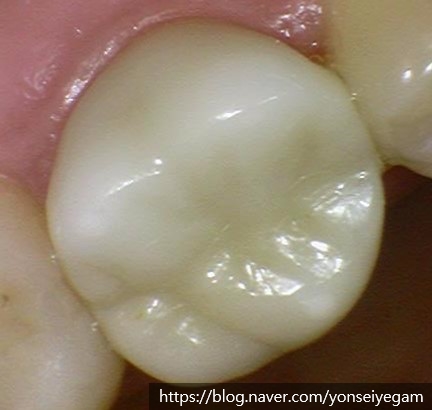

![시청역치과 [Q&A]다른치과에서 한 인레이,크라운,임플란트에 음식물이 껴요 관련 이미지 6](https://pub-9f2bb3498faf4d1d8714b41df24753e3.r2.dev/content/clinics/archive/rseeanjxfu/naver_blog/yonseiyegam/assets/by_hash/244839b0b27eb8b7b7754b35d8696d2eb01f61639e95759531cf370ba01dfc60.jpg)

꾸준히 저희 시청역 연세예감치과에서 검진을 받으시면서 크라운을 한지 3년이 되었는데 잘 유지되고 관리되는 모습을 보이고 있습니다.

아래 사진은 옆에서 본 모습입니다.

지르코니아 크라운은 치아와 색도 유사하여 골드크라운과 달리 크라운 했다는 티도 겉으로 나지않고, 생체친화적이며, 강도도 우수하여 많은 환자분들이 관리만 잘 된다면 오래 사용하고 계십니다.

위의 지르코니아 크라운 케이스는 완성까지

내원횟수 : 2회, 내원기간: 5일 소요되었습니다.

더이상 음식물이 끼지 않아 잇몸도 건강하게 관리되며, 음식물이 끼어서 뒷치아까지 충치가 생기는 일을 방지해주었습니다.